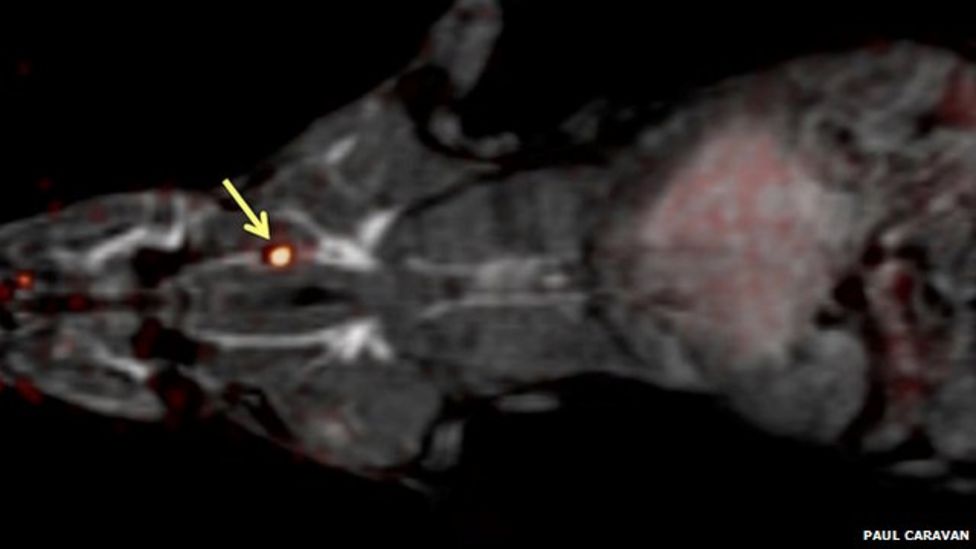

From www.bbc.co.uk

New probe 'lights up' blood clots in single scan BBC News Does Blood Clots Show Up On Xrays Your doctor will likely perform a physical examination, and you may undergo a venous ultrasound or a ct angiography (cta) scan of the. Pulmonary embolisms can reduce oxygen in. Venography, which uses a dye to show blood flow in the veins. In addition, blood tests may be done to determine whether you have an inherited clotting disorder. For example, in. Does Blood Clots Show Up On Xrays.